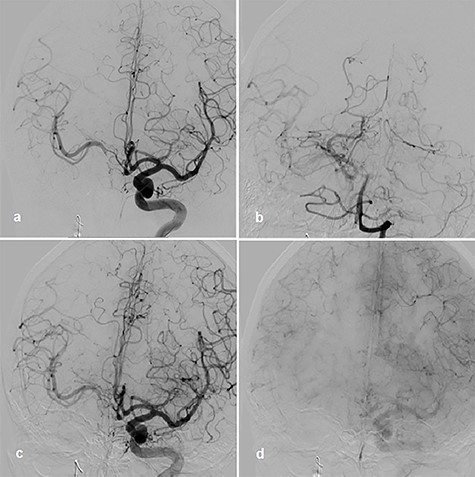

Afterward, we decided to perform aneurysm coiling and PAO. Prior to this, we repeated the occlusion test with clinical, angiographic and TCD control before and during induced arterial hypotension. In stand-by anesthesia with central venous catheter and invasive blood pressure monitoring, a 4-F catheter was placed in the left ICA and a 6-F guiding catheter was placed in the right ICA. Occlusion of the right ICA was performed with a balloon. With 100 mmHg mean blood pressure, we measured 78 m/s systolic flow in the TCD on the right MCA. The patient presented no neurological symptoms. Left ICA angiogram showed good crossflow perfusion of the right side over the anterior communicating artery. After a drop of mean blood pressure from 100 to 70 mmHg using intravenous administration of urapidil, there was no neurological deficit observed over the period of 30 min. Furthermore, there was no perfusion reduction and no delay of venous phase on the right side on the angiogram of left ICA (Fig. 2c and d), but we observed systolic flow reduction from 78 to 50 cm/s on the right MCA in the TCD during induced arterial hypotension. Based on the results of good collateral flow during occlusion test without neurological deterioration after hypotension challenge, we finally performed PAO by coiling with seven coils (Fig. 3a).

Coiling of giant aneurysm and parent vessel occlusion, p–a angiogram (a), CT scan on Day 1 (b).

After aneurysm coiling with PAO, the patient was put on dual antiaggregation therapy with aspirin 100 mg and clopidogrel 75 mg per day for the next 6 weeks, followed by aspirin alone 100 mg per day lifelong. Computed tomography (CT) scan on Day 1 presented no infarction (Fig. 3b). Perfusion CT scan on Day 9 after intervention showed regular perfusion of the right hemisphere without any cerebral blood flow/cerebral blood volume mismatch. The oculomotor palsy had subsided after 3 months.